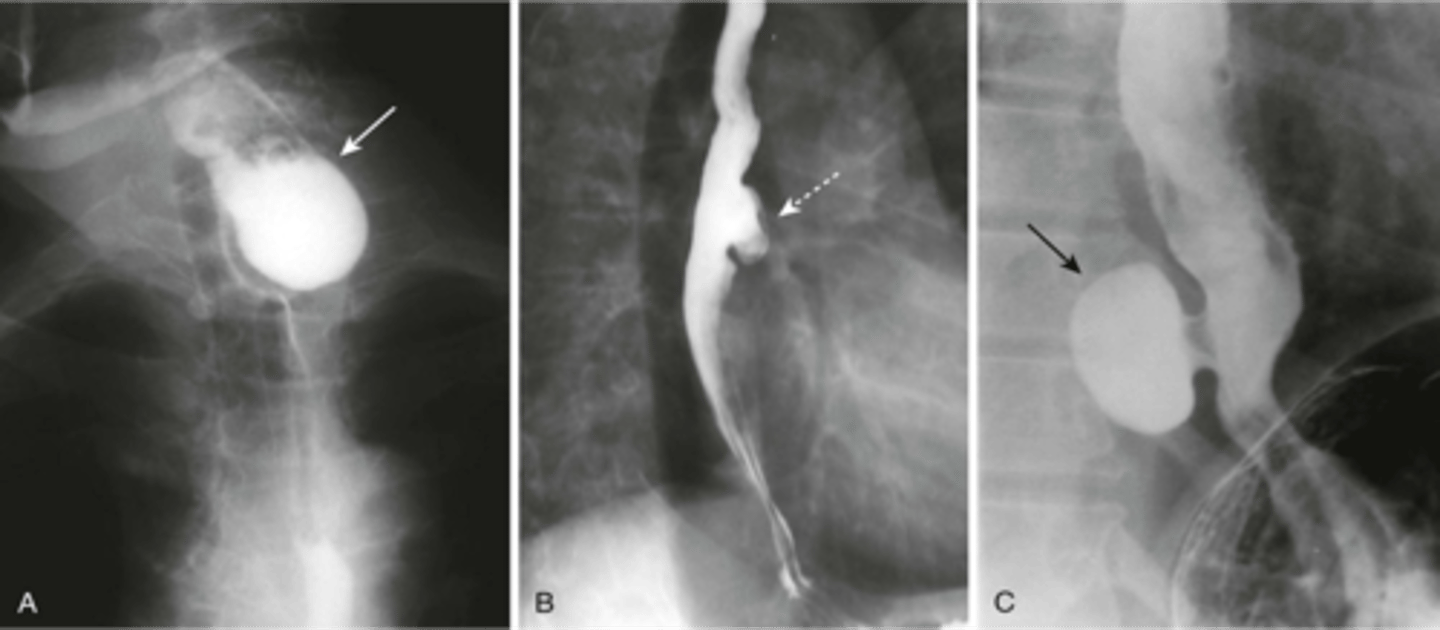

A: zenkers diverticulum

B: traction diverticulum (often seen in TB patients)

C: epiphrenic diverticulum